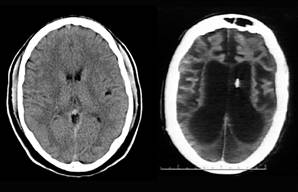

The image on the left is a normal brain, the image on the left was Terri's brain in 2002, the massive black areas are where her brain had turned to soup. She didn't die until 2005, 3 years later.